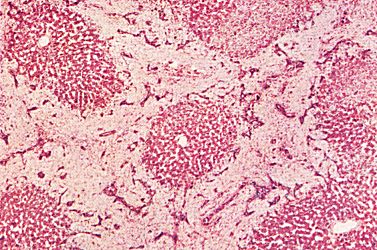

The following slide is of a cross section of the liver. Pig liver has more pronounced connective tissue septae and is used here to demonstrate the septae.

Fig 68-001 |